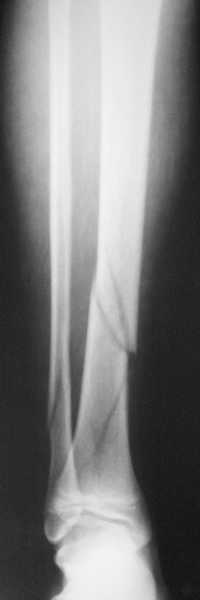

В приложении метафизарный перелом у ребёнка 14лет, с распространением линии перелома на зону роста.